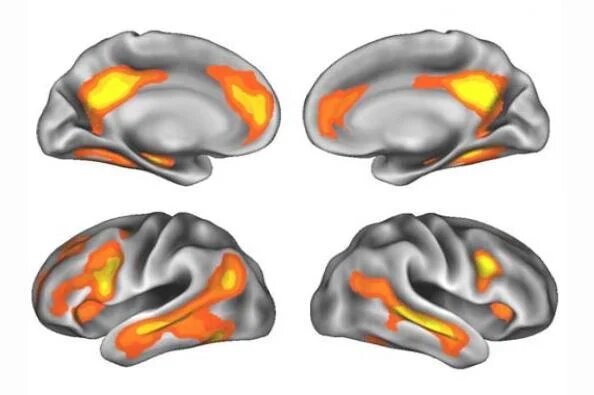

در طول بارداری اول، بزرگترین تغییرات در شبکه حالت پیشفرض یا دروننگر (default sate network) ظاهر شد که در خوداندیشی، پردازش عاطفی و تعامل اجتماعی نقش دارد.

بر اساس یافتههای این مطالعه، در طول بارداری دوم، تغییرات بیشتری در شبکههایی که در توجه و پاسخ به نشانههای حسی نقش دارند، ظاهر شد.

به گفته این پژوهشگران، این فرآیندها ممکن است هنگام مراقبت از چندین فرزند مفید باشند.